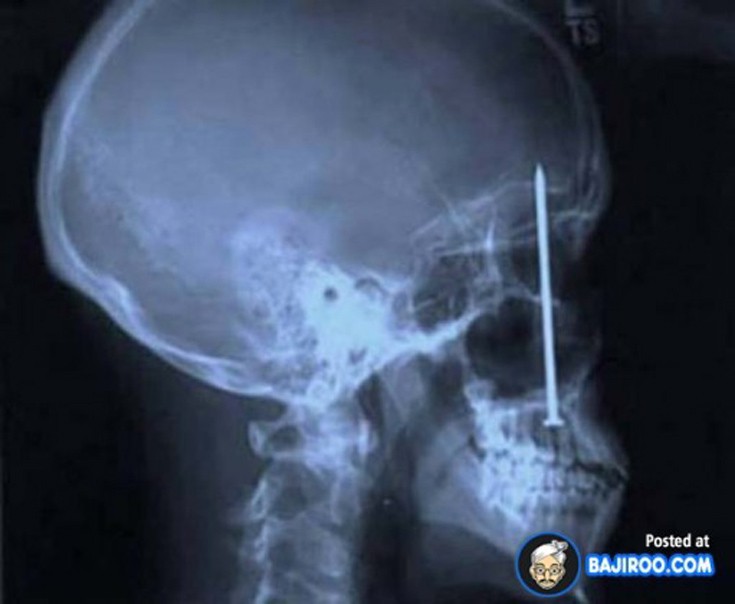

Ο,ΤΙ ΝΑ 'ΝΑΙ #ακτινογραφίες Παράξενα πράγματα που έχουν δείξει οι ακτινογραφίες Από δαχτυλίδια μέχρι πιρούνια και καρφιά - Δείτε τις φωτογραφίες 15·04·2016 11:08 1 σχόλια